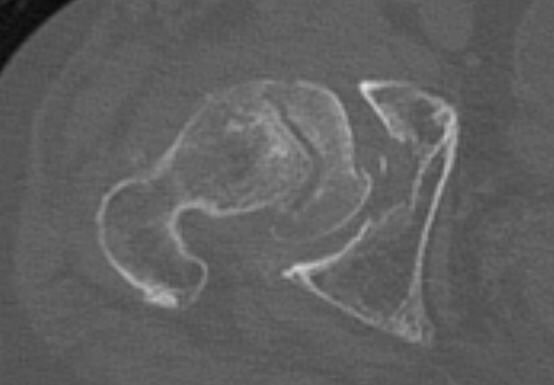

ところが、THA前提で単純X線像とCTを施行したところ、大腿骨頚部骨折を発症しているではないですか!前医でMRIを撮像してから 2週間の間に骨折が顕在化したようです。

いわゆる大腿骨頚部不顕性骨折と思われます。何年かに一度ぐらいの割合で大腿骨頚部不顕性骨折を診ますが、最初のMRIでは骨折線が判然としないことがネックだと感じました。